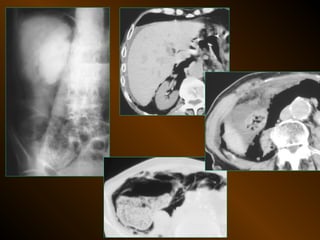

• X QUANG CẮT LỚP ĐIỆN TOÁN

– Mật độ

– Vị trí

– Nguyên nhân